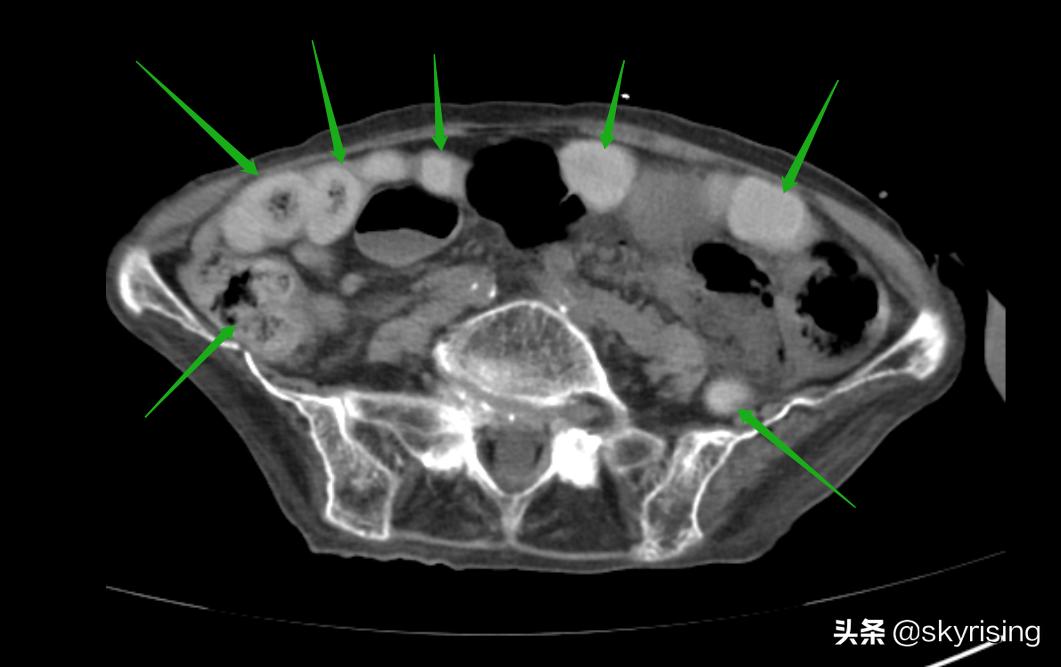

下图黄色箭头所示小肠回肠肠襻呈U型改变,肠管扩张,肠壁增厚,肠壁间见垂直线性气体密度影。这是典型肠系膜血管栓塞的典型表现,可能是动脉也可能是静脉,需要结合增强检查。